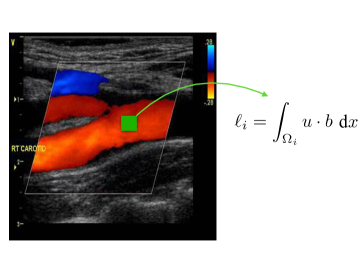

where the are linearly independent linear forms over . In many applications, each models a sensor device which is used to collect the measurement data . In our particular application, the observations come in the form of an image and each models the response of the system in a given pixel as Figure 2 illustrates. We denote by the Riesz representers of the . They are defined via the variational equation

Our goal is to reconstruct for all time on an interval (with ) the full 3D velocity field and pressure in the whole carotid . Additionally, we also want to reconstruct related quantities like the wall-shear stress, the vorticity and the pressure drop between the inlet and the outlets. The Doppler ultrasound device gives images with a certain time frequency. Each image contains partial information on the blood velocity in a subdomain of the carotid. Depending on the ultrasound technology, we are either given the projection of the velocity along the direction of the ultrasound probe (CFI mode), or along a plane (VFI mode). Figure 2 illustrates both imaging techniques.

Due to our lack of real images, our experiments are fully synthetic, and we work with an idealized version of CFI images to generate measurements. For each time , a given image is a local average in space of the velocity projected onto the direction in which the ultrasound probe is steered. More specifically, we consider a partition of into disjoint subdomains (voxels) . Then, from each CFI image we collect

| (2.6) |

where is a unitary vector giving the direction of the ultrasound beam. According to what has been exposed in section 2.1, the are linear functionals from a certain Hilbert space which, in our case, is yet to be defined.